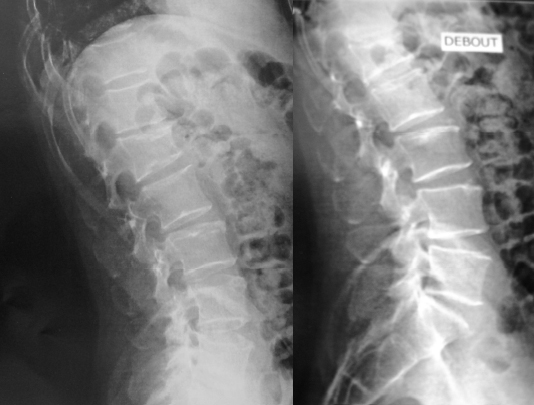

L’homme est complexe

Dr Jacques Fechtenbaum Hôpital Cochin - Paris

Mr F. né en 1964 est employé dans un magasin de grande distribution. Il a présenté une dorsalgie basse lors d’un effort de soulèvement.

Des radiographies du rachis dorso-lombaire sont demandées.

Voici les clichés.

Le compte rendu radiologique note :